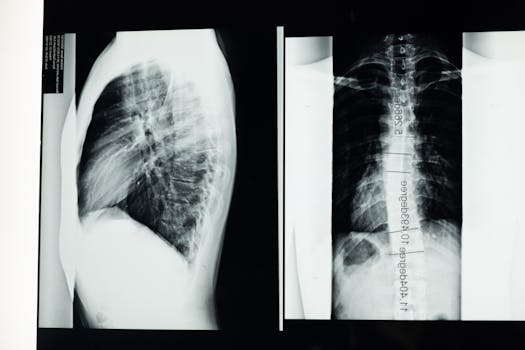

When it comes to managing scoliosis, one of the most frequently discussed treatment options is the scoliosis brace. This supportive device is designed to prevent further curvature of the spine in patients diagnosed with scoliosis, particularly during their growth spurts. If you or a loved one has been advised to use a scoliosis brace, understanding…